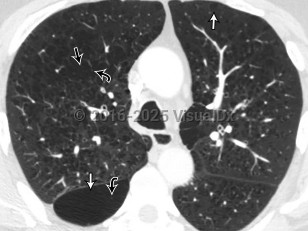

Pulmonary emphysemaPulmonary emphysema